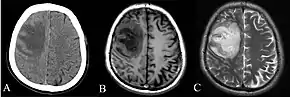

Depending on the course of infection, other severe manifestations develop. About 1 to 5% of those infected develop inflammation of the brain and brain covering or collection of pus in the brain; 14 to 28% develop bacterial inflammation of the kidneys, kidney abscess or prostatic abscesses; 0 to 30% develop neck or salivary gland abscesses; 10 to 33% develop liver, spleen, or paraintestinal abscesses; 4 to 14% develop septic arthritis and osteomyelitis.[1] Rare manifestations include lymph node disease resembling tuberculosis,[7] mediastinal masses, collection of fluid in the heart covering,[3] abnormal dilatation of blood vessels due to infection,[1] and inflammation of the pancreas.[3] In Australia, up to 20% of infected males develop prostatic abscess characterized by pain during urination, difficulty in passing urine, and urinary retention requiring catheterisation.[1] Rectal examination shows inflammation of the prostate.[3] In Thailand, 30% of the infected children develop parotid abscesses.[1] Encephalomyelitis can occur in healthy people without risk factors. Those with melioidosis encephomyelitis tend to have normal computed tomography scans, but increased T2 signal by magnetic resonance imaging, extending to the brain stem and spinal cord. Clinical signs include: unilateral upper motor neuron limb weakness, cerebellar signs, and cranial nerve palsies (VI, VII nerve palsies and bulbar palsy). Some cases presented with flaccid paralysis alone.[3] In northern Australia, all melioidosis with encephalomyelitis cases had elevated white cells in the cerebrospinal fluid (CSF), mostly mononuclear cells with elevated CSF protein.[7]

Various imaging modalities can also help with the diagnosis of melioidosis. In acute melioidosis with the spreading of the bacteria through the bloodstream, the chest X-ray shows multifocal nodular lesions. It may also show merging nodules or cavitations. For those with acute melioidosis without the spread to the bloodstream, chest X-ray shows upper-lobe consolidation or cavitations. In chronic melioidosis, the slow progression of upper-lobe consolidation of the lungs resembles tuberculosis. For abscesses located in other parts of the body apart from the lungs, especially in the liver and spleen, CT scan has higher sensitivity when compared with an ultrasound scan. In liver and splenic abscesses, an ultrasound scan shows "target-like" lesions, while CT scan shows "honeycomb sign" in liver abscesses. For melioidosis involving the brain, MRI has higher sensitivity than a CT scan in diagnosing the lesion. MRI shows ring-enhancing lesions for brain melioidosis.[7]